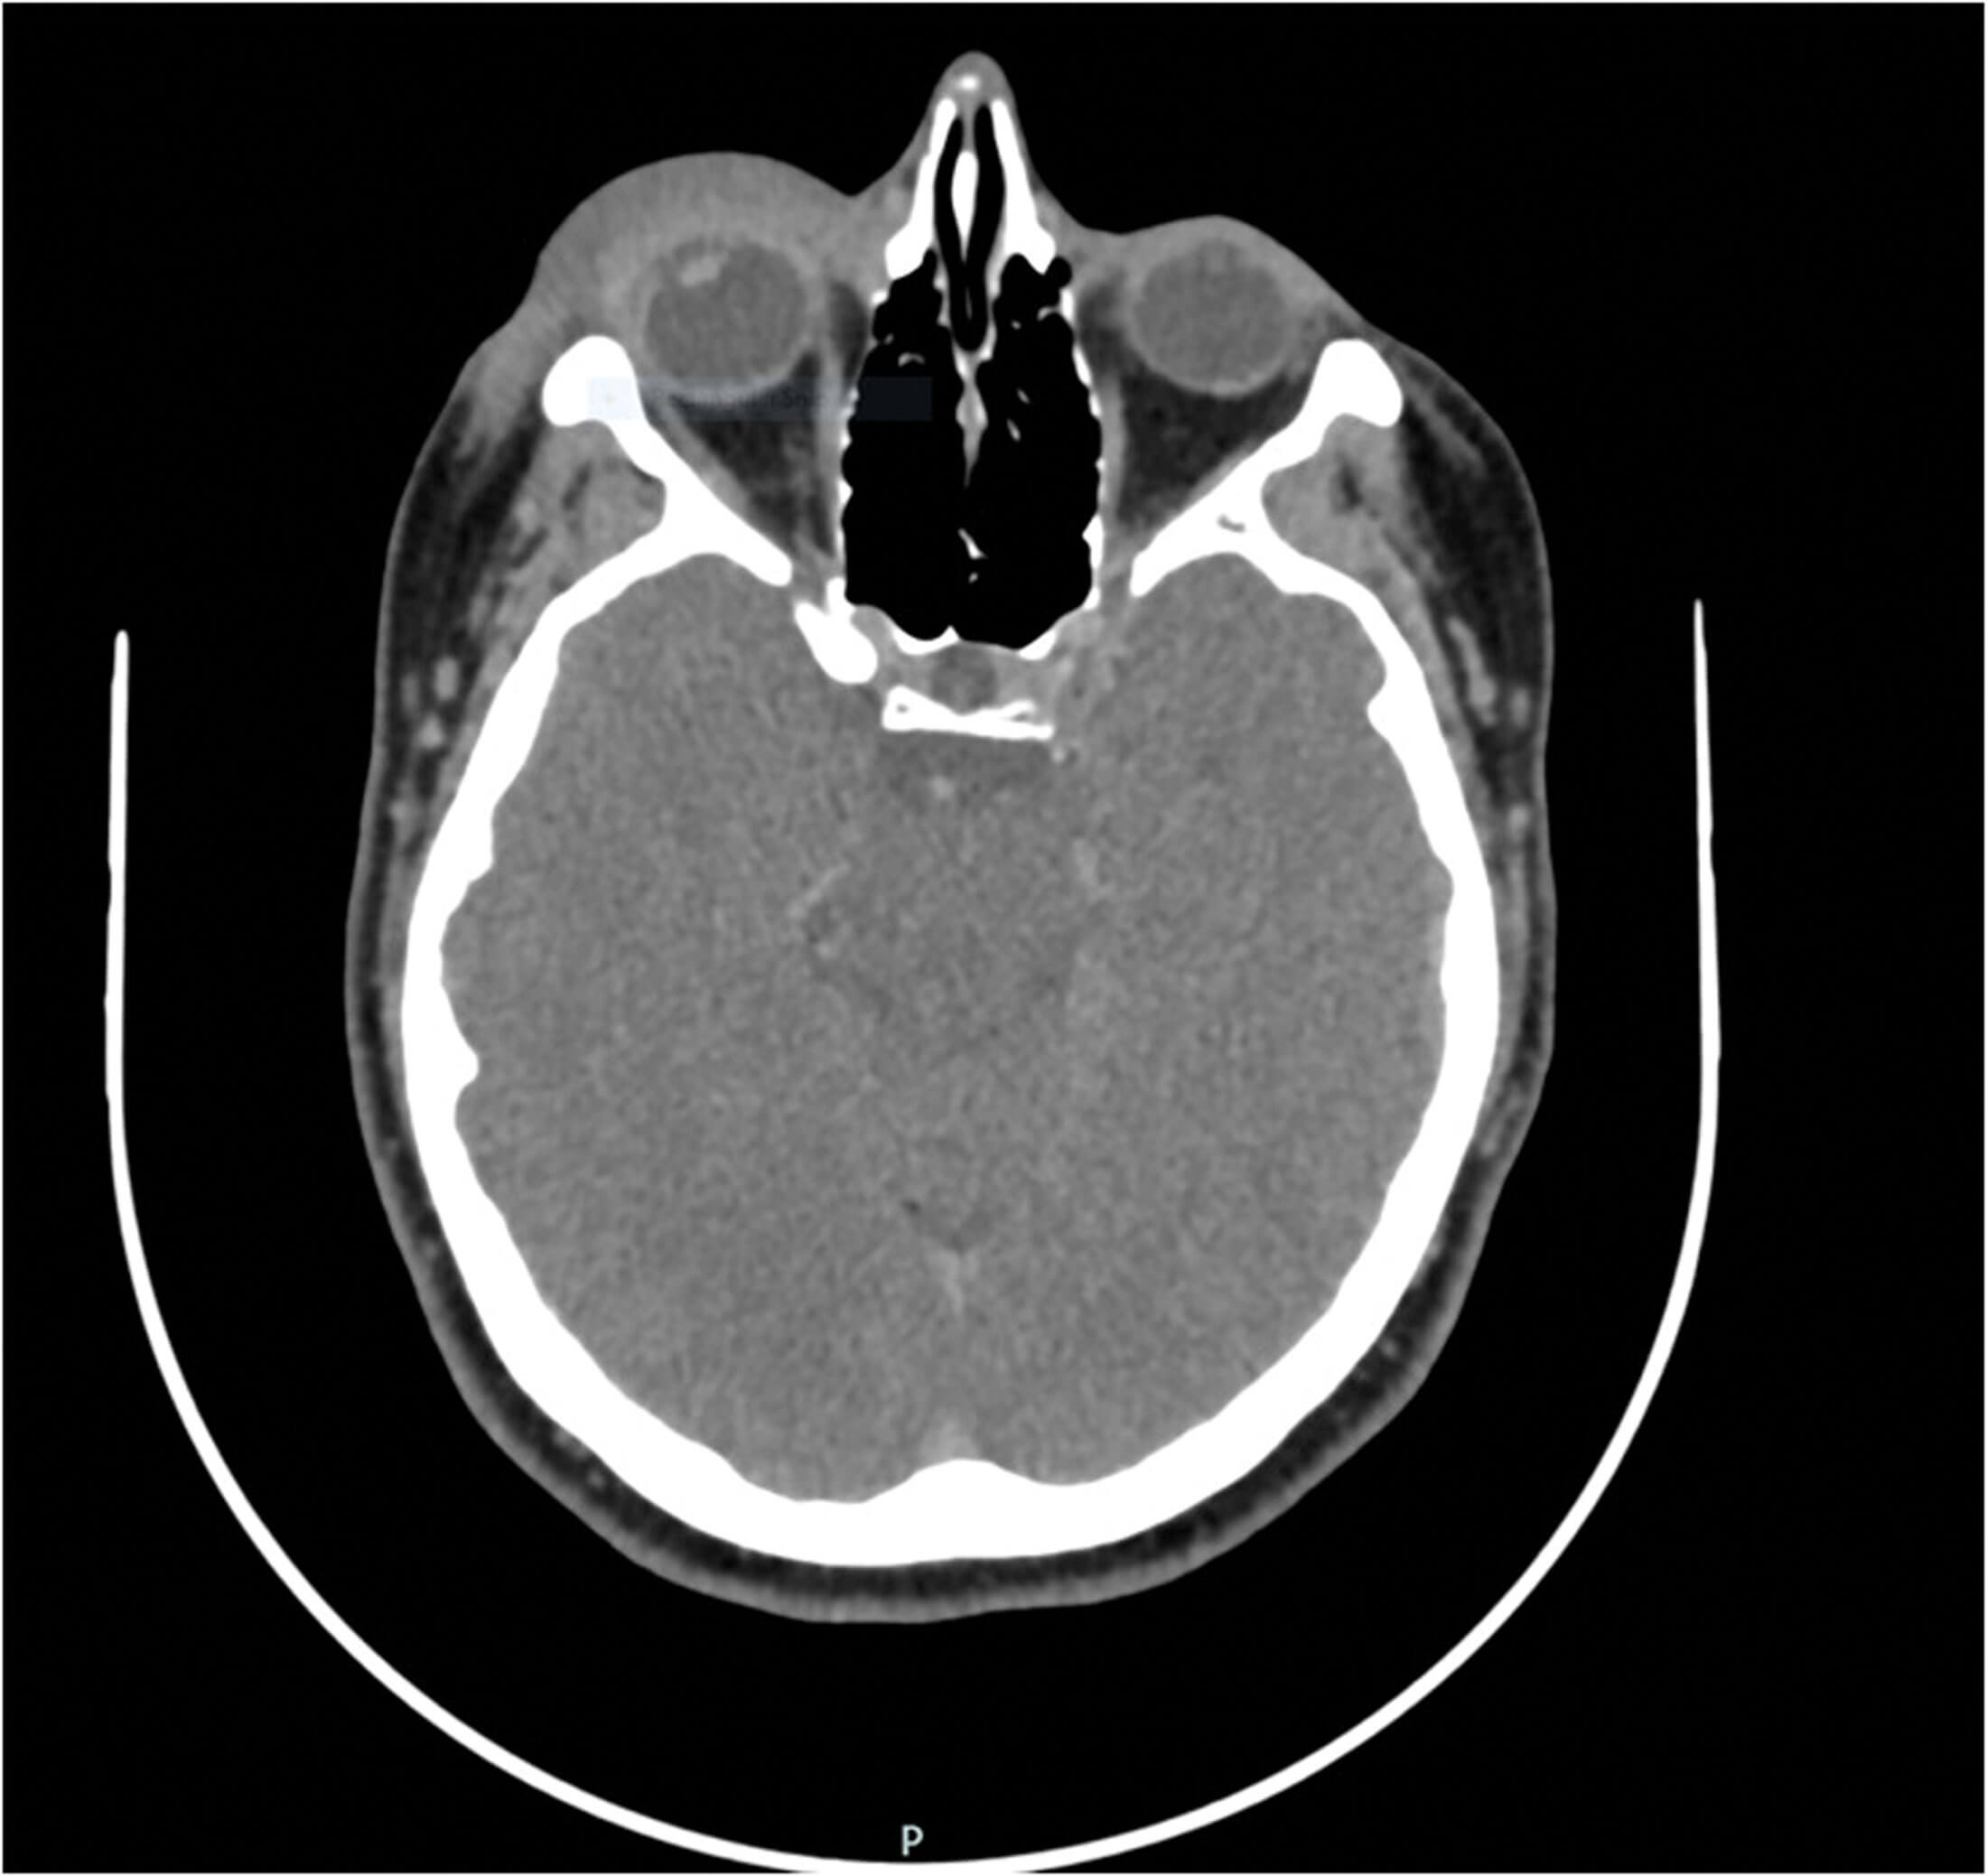

Figure 3: Right eye CT scan image showing periorbital soft tissue swelling mainly.

The case was discussed in the regional orbital multidisciplinary team (MDT) meeting with review of her orbital imaging. She had the initial CT scan of orbits and sinuses done in 2013 and a repeat scan with IV contrast in 2019. Both times the scan was done after most of her clinical signs had resolved, hence there was no significant pathology seen (Figure 3). The consensus of the MDT was the same, that there was no abnormality seen.